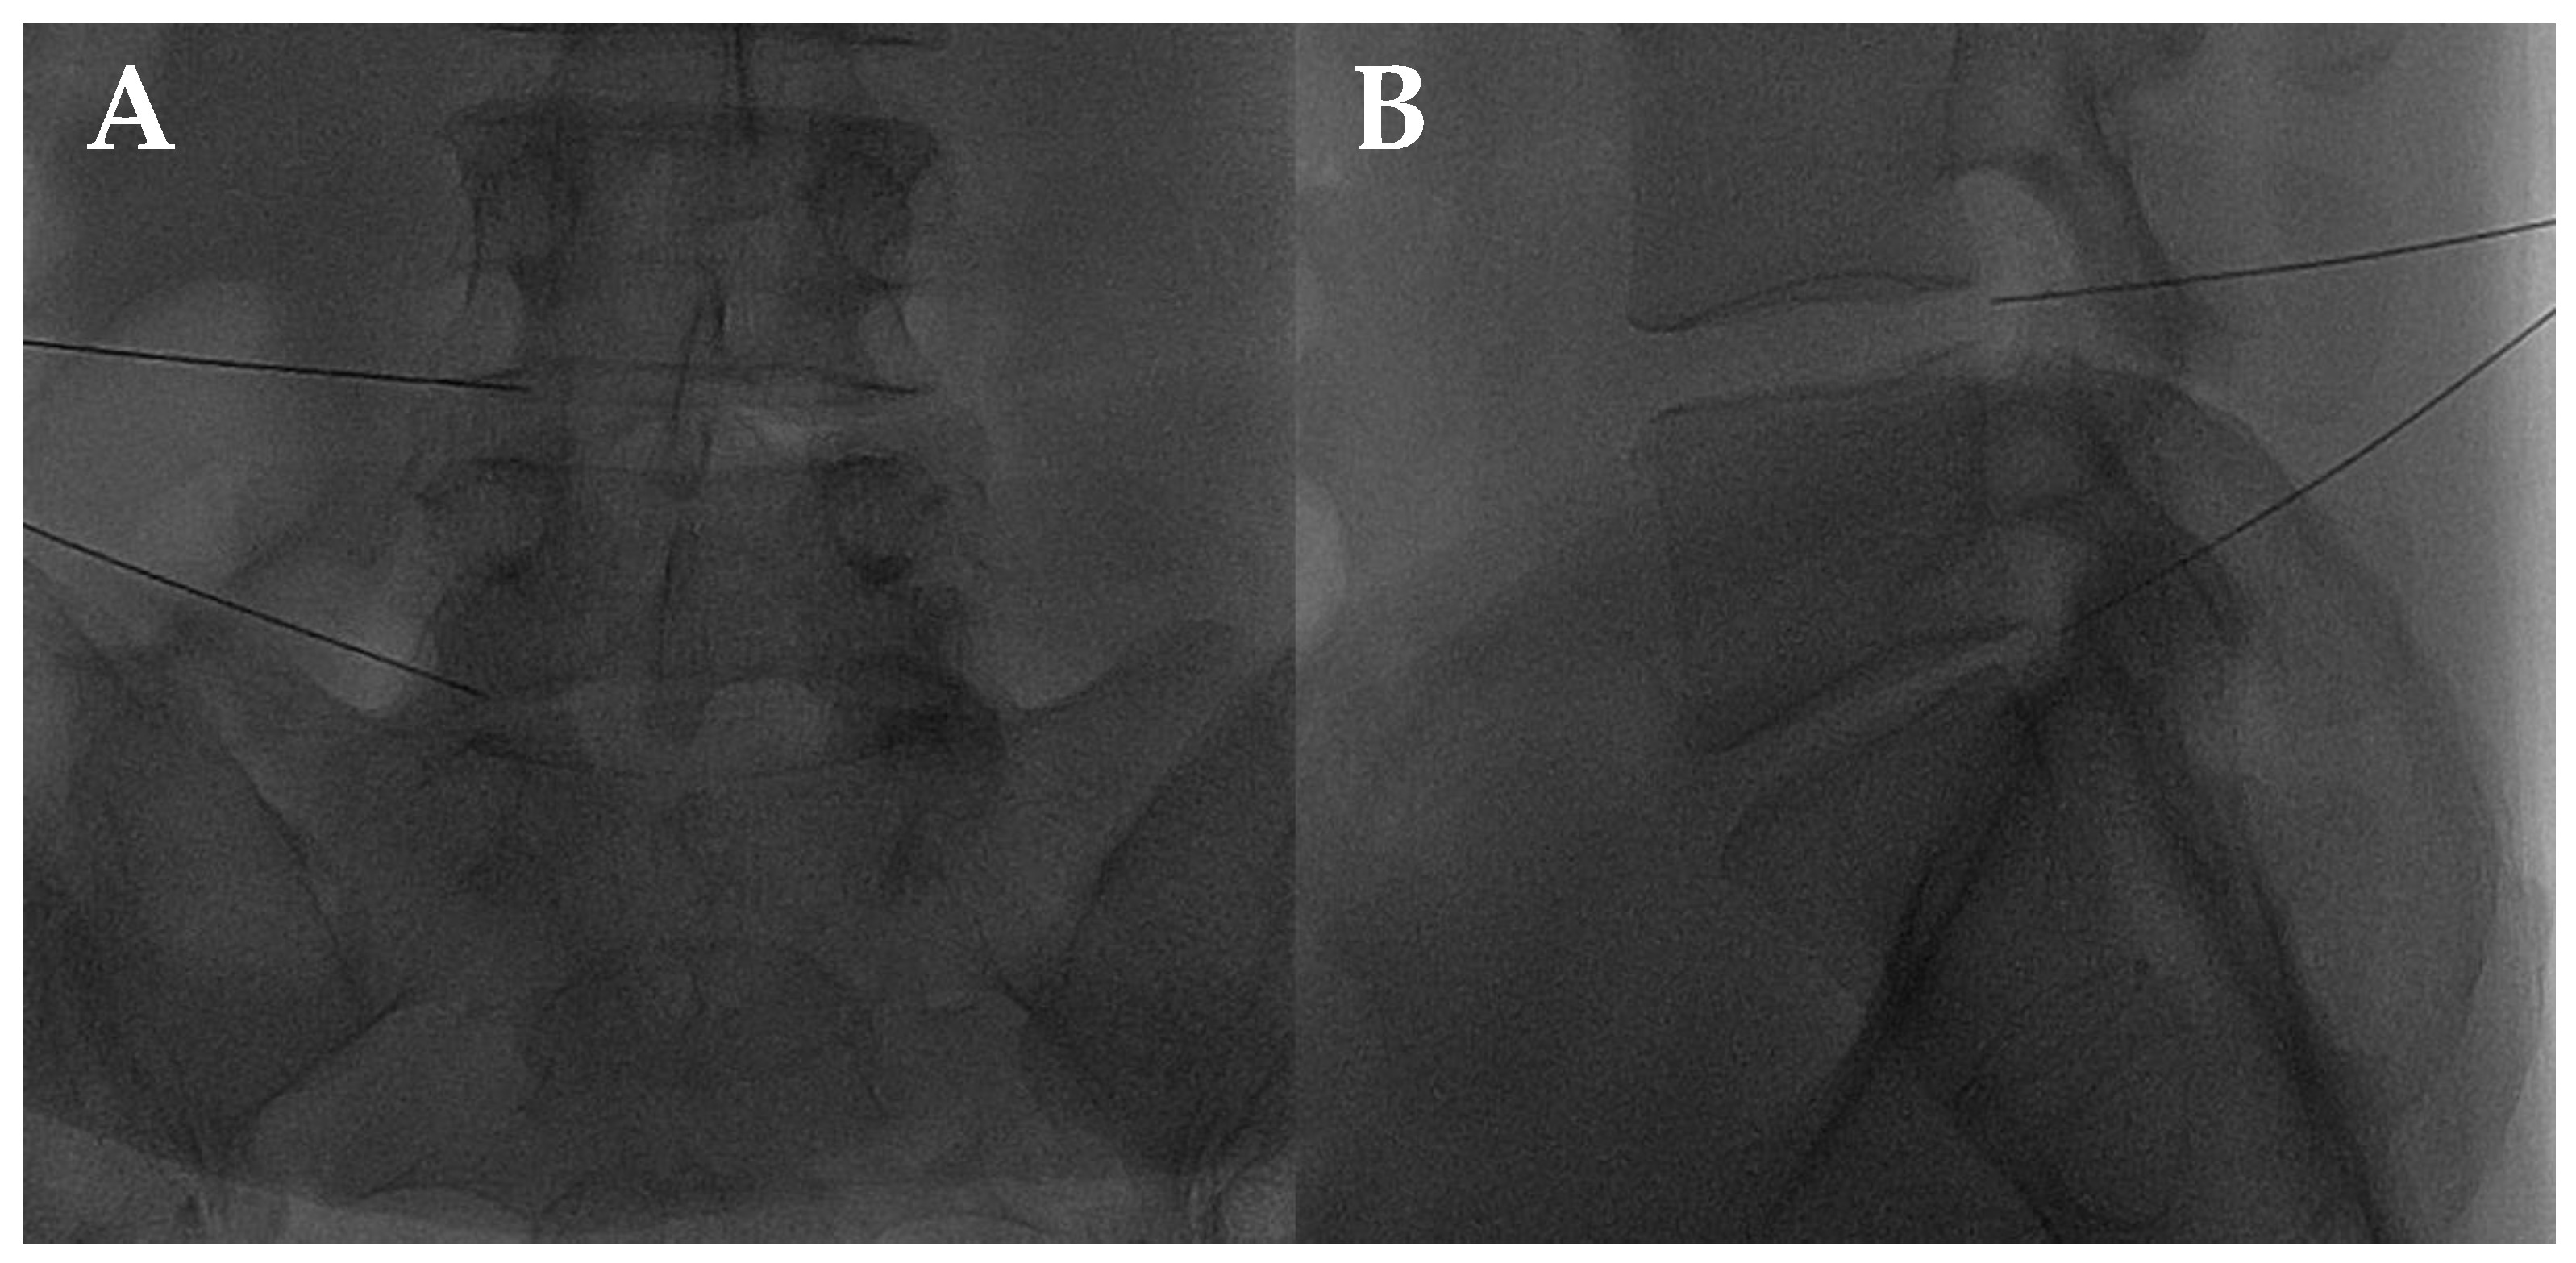

The disc center is the ideal injection target, and the prone position, employing support under the abdomen or the neck to increase the posterior vertebral space, is the optimum posture to expand the intervertebral space [48]. The access site is always selected after radiographic evaluation of the needle path; it is suggested to follow a lateral inclination of 45° to 60°, with an additional craniocaudal inclination for lumbar discs [56,57]. Some authors indicate the foramen radicularis, maintaining the root laterally and superiorly, as the best way to access the center of the disc (Figure 2 and Figure 3) [58].

Figure 2.

(A,B) Lateral and frontal view on fluoroscopic images of a lumbar intersomatic disc puncture with a 22G needle.